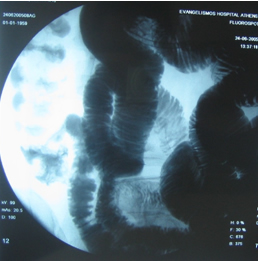

Στους ίδιους ασθενείς η εντερόκλυση μπορεί να αναδείξει ανάλογα ευρήματα με την ενδοσκοπική κάψουλα (εικόνες 36-43) ή να είναι φυσιολογική (εικόνες 44-48).

42  43

Εικόνα 42. Ο ίδιος ασθενής με την εικόνα 11.                Εικόνα 43. Ίδιος ασθενής με τις εικόνες 18-20.

Οδόντωση τελικού ειλεού από πολλαπλά                      Οίδημα και έλκη τελικού ειλεού

έλκη